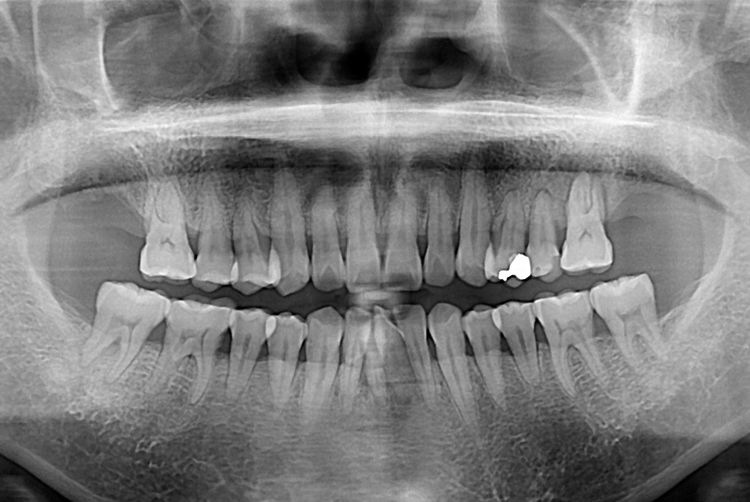

송수덕_후.jpg

치료후 : 2017-07-31

세종치과는 많은 환자와 다양한 케이스를 바탕으로 항상 편안한 임플란트 수술을 제공하고자 노력하고,

오래동안 튼튼히 쓸 수 있는 임플란트 수술을 가장 큰 목표로 삼고 있습니다.